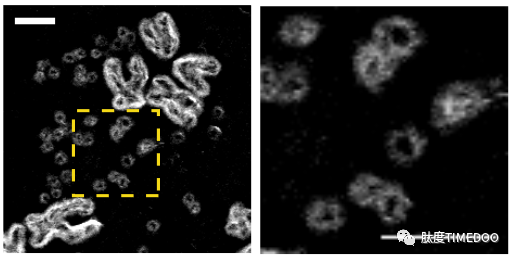

2019年11月21日,吴思涵在《Nature》杂志发表的文章《Circular ecDNA promotes accessible chromatin and high oncogene expression》中,首次揭示了携带癌基因的染色体外ecDNA的物理结构与生物学功能。这一发现不仅改写了我们对癌症遗传学的认知,也震动了全球科研界。【查看独家专访】

2020年,吴思涵参与的5000例临床全基因组测序研究进一步展示了肿瘤环状DNA的全貌,引领了ecDNA研究的热潮。其成果在《Nature Genetics》杂志发表,标志着ecDNA研究的重大进展。【查看独家专访】

2021年8月14日,吴思涵的国内首场肿瘤ecDNA学术报告在肽度TIMEDOO举办,聚焦ecDNA的分子特征、功能、起源、研究方法等问题,系统性地梳理了过去50年间围绕ecDNA的研究成果,并重点解读了近5年的突破性进展。【点击阅读原文】